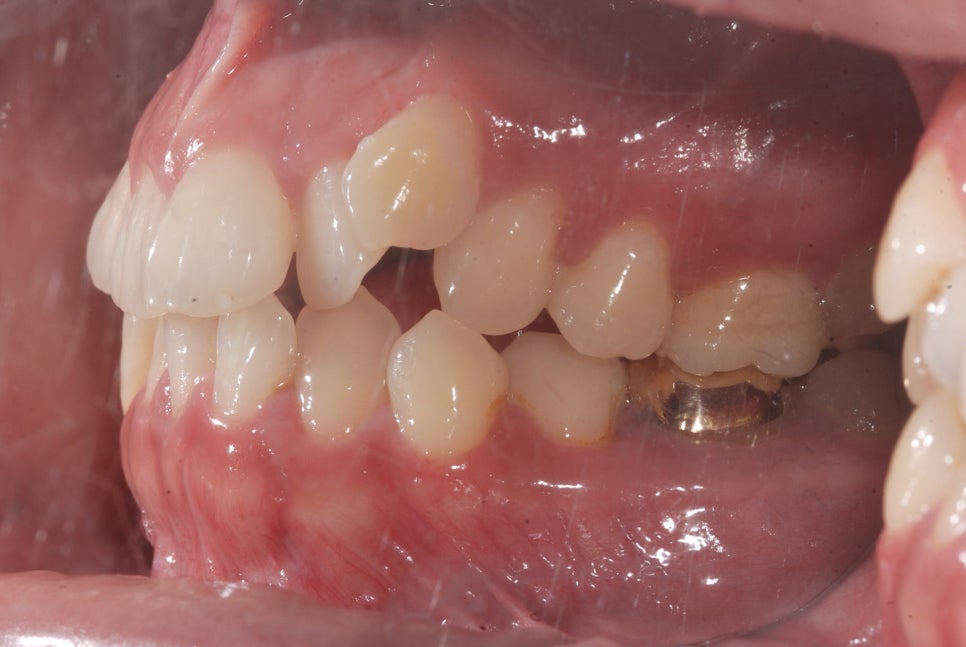

또 덧니가 심하게 겹쳐 있거나 교합이 맞지 않는 경우에는

덧니 라미네이트만으로는 근본적인 해결이 어렵기도 합니다.

덧니 교정은 치아 자체를 움직여서 배열을 바르게 만드는 치료인데요.

왜냐하면 덧니는 '보기 안 좋다'의 문제가 아니라,

구강 관리가 어렵고 충치나 잇몸질환이 잘 생기는 구조적 문제를 동반하기 때문입니다.

교정 치료를 통해 덧니를 가지런히 배열하면

심미적인 개선뿐 아니라 구강 건강까지 동시에 잡을 수 있는 건데요.